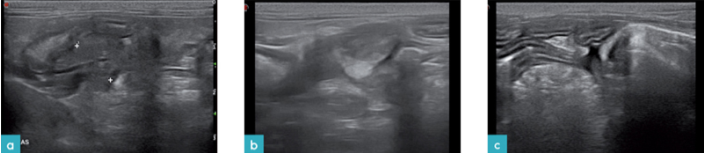

猫发生急性胰腺炎的超声表现与犬类似。胰腺呈低回声或是混合回声,胰腺体积广泛性增大,胰腺周围脂肪回声增强(脂肪的皂化反应),存在游离液体(图9和10)。然而,发生急性胰腺炎的猫并不都发生这些超声表现。

一些研究表明fPLI(猫胰腺特异性脂肪酶)的诊断结果与胰腺的超声学改变有着较好的相关性。诊断胰腺炎需要综合评估,超声影像左侧胰腺炎实质增厚,边缘不规则,周围脂肪低回声,存在临床症状,fPLI升高,可以判定为发生了胰腺炎。

猫慢性胰腺炎的发病率比急性胰腺炎高。慢性胰腺炎的组织病理学是以纤维化和无菌性炎症为特征的。胰腺的超声改变很细微或是几乎无改变(图11)。胰腺可能边界清晰呈低回声,在纤维化的区域呈高回声(图12)。偶尔也会发现胰腺边界不规则,实质内有钙化灶。然而,研究表明超声不能区分慢性非化脓性胰腺炎和急性坏死性胰腺炎。